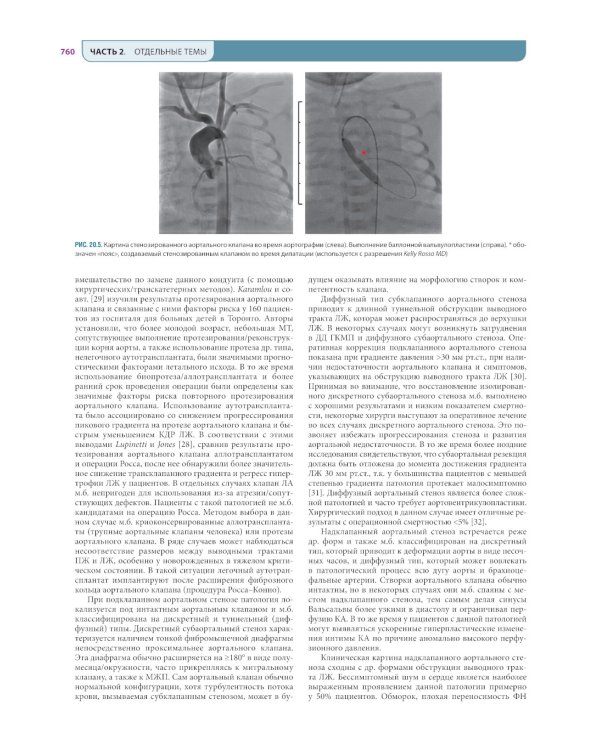

Перед вами перевод 11-го издания фундаментального руководства "Хирургия по Шварцу". Эта книга с полувековой историей является бестселлером, самым полным, достоверным и передовым ресурсом для нескольких поколений хирургов во всем мире, и теперь она впервые переведена на русский язык. Руководство охватывает широкий спектр вопросов хирургии: от основ организации помощи при необходимости хирургического лечения и фундаментальных и прикладных аспектов лечения пациентов до наиболее актуальных медико-социальных проблем. Именно поэтому оно будет полезно не только хирургам, но и широкому кругу врачей смежных специальностей. Издание выполнено под общей редакцией академика РАН А.Ш. Ревишвили, академика РАН Ю.В. Белова и профессора В.И. Белоконева в сотрудничестве со специалистами из ведущих профильных медицинских организаций Российской Федерации: Национального медицинского исследовательского центра хирургии им. А.В. Вишневского и Российского научного центра хирургии им. акад. Б.В. Петровского. Текст руководства доработан к использованию в Российской Федерации и дополнен комментариями на основании принятых в нашей стране клинических рекомендаций и других нормативных документов. Издание содержит свыше 800 фотографий и 1300 рисунков (большинство из них цветные), сотни таблиц, графиков и схем, а также QR-коды, которые ведут к дополнительным источникам информации и библиографии. "Хирургия по Шварцу" - это современный, надежный и авторитетный источник знаний не только для хирургов, но и для широкого круга врачей-специалистов, издание также будет полезным ординаторам, аспирантам и студентам медицинских вузов.